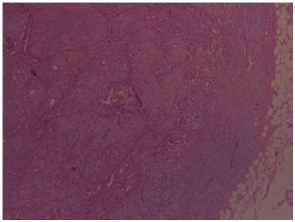

The pathology report revealed presence of lymphoepithelial carcinoma of the right parotid gland with positive lymph nodes from specimens taken. Upon performing pathological studies, the sample excised was stained with hematoxylin and eosin stain (Figure 3) which showed lymphocytic infiltrates invading the parotid gland, EBER stain (Figure 4) showed positive results for presence of Epstein bar virus. The excised lymph nodes were also stained (Figure 5), and metastasis was found.

Figure 3 Parotid gland with marked lymphocytic infiltrates (H & E, 4X).